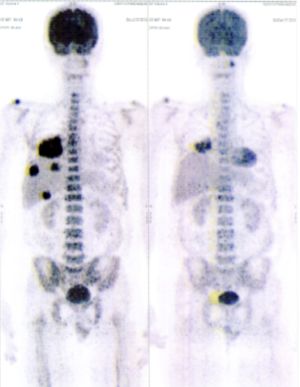

Below are some of the cases, from more than 80 cases we have treated so far with good results. When reading the PET/CT scans, the picture on the left is before treatment, and the picture on the right is after treatment. The intensity of black represents the activity of the cancer, but some black areas are not cancer: brain, heart, radioactive urine in bladder. For the heart, the intensity of black depends on the number of hours of fasting: if more than 10 hours, the heart is not even black, but if fasting is less than 6 hours, it is very black. The intensity of black in the brain can be variable in different scans depending on the brain activity at the time of the scan. The intensity of black in the radioactive urine can also be variable due to the hydration of patients and the time of injection of diuretic.

CASE NO: 34 (PERIPHERAL T-CELL LYMPHOMA)

A 50+ year old female has recurrent Peripheral T-Cell Lymphoma that failed all treatment, and it has spread to lymph nodes in the axillary and mediastinal region, and to the lungs. The specialists gave her about 3 months to live. After just one treatment, the axillary/mediastinal nodes and the lung lesions are gone. One set of pictures shows the lymph nodes, and the other set of pictures show lung lesions. The picture on top is BEFORE TREATMENT, and the picture below is AFTER TREATMENT.

CASE NO: 34 AFTER TREATMENT